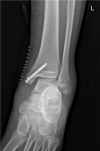

Case summary: A 16-year-old patient sustained left medial malleolar fracture, and the associated inferior tibiofibular syndesmotic instability was overlooked. After open reduction and internal fixation of the medial malleolar fracture, inferior tibiofibular syndesmosis diastasis with IOM rupture was detected by auxiliary imaging. Secondary surgical intervention was performed to reduce anatomically and fix with two trans-syndesmosis screws. Twelve weeks later, the screws were removed. At the 6-mo follow-up, the patient gained full range of motion of the ankle.